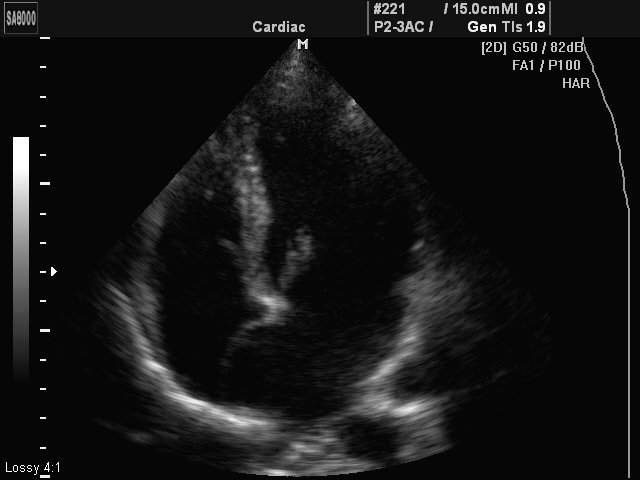

Aneurismus interatrium septum, B-mode

Aneurismus interatrium septum, B-mode (echogramm №428)

[RU] Ultrasound image №428: Heart (aneurismus interatrium septum) in B-mode.

Echogramm was received by ultrasound scanner SonoAce-8000 (out of production).